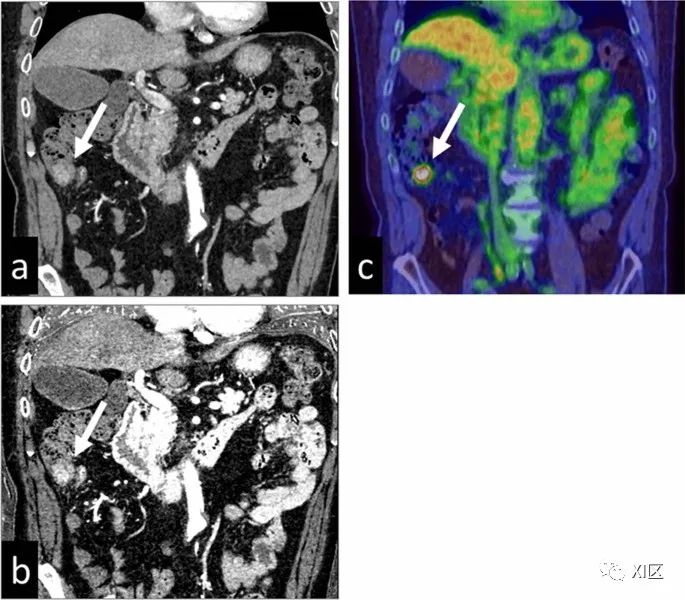

在碘图上,胃和结肠肿瘤的可检测性得到了改善(图15),恶性和良性病变的鉴别也得到了改善。碘图像也适用于急腹症患者,如小肠缺血或胃肠道出血。它们增加肠壁低衰减段的显著性,从而潜在地改善缺血的早期检测。它们还可以帮助识别造影剂外渗的细微区域,以便准确定位胃肠道出血的来源。

图15 71岁男性患有升结肠癌。显示了动脉期70 keV(a)下的虚拟单色图像和碘图(b)。碘图比单色70keV图像更显眼。(c)PET-CT图像(肿瘤的最大标准化摄取值为6.1)增强双能量CT扫描对于血管内主动脉修复术(EVAR)后的内漏检测有价值。在较低能量下获得的VMI会增加血管对比度,而晕染和金属伪影会降低图像质量。另一方面,碘图在不增加晕影的情况下提高了内漏的显著性(图16)。